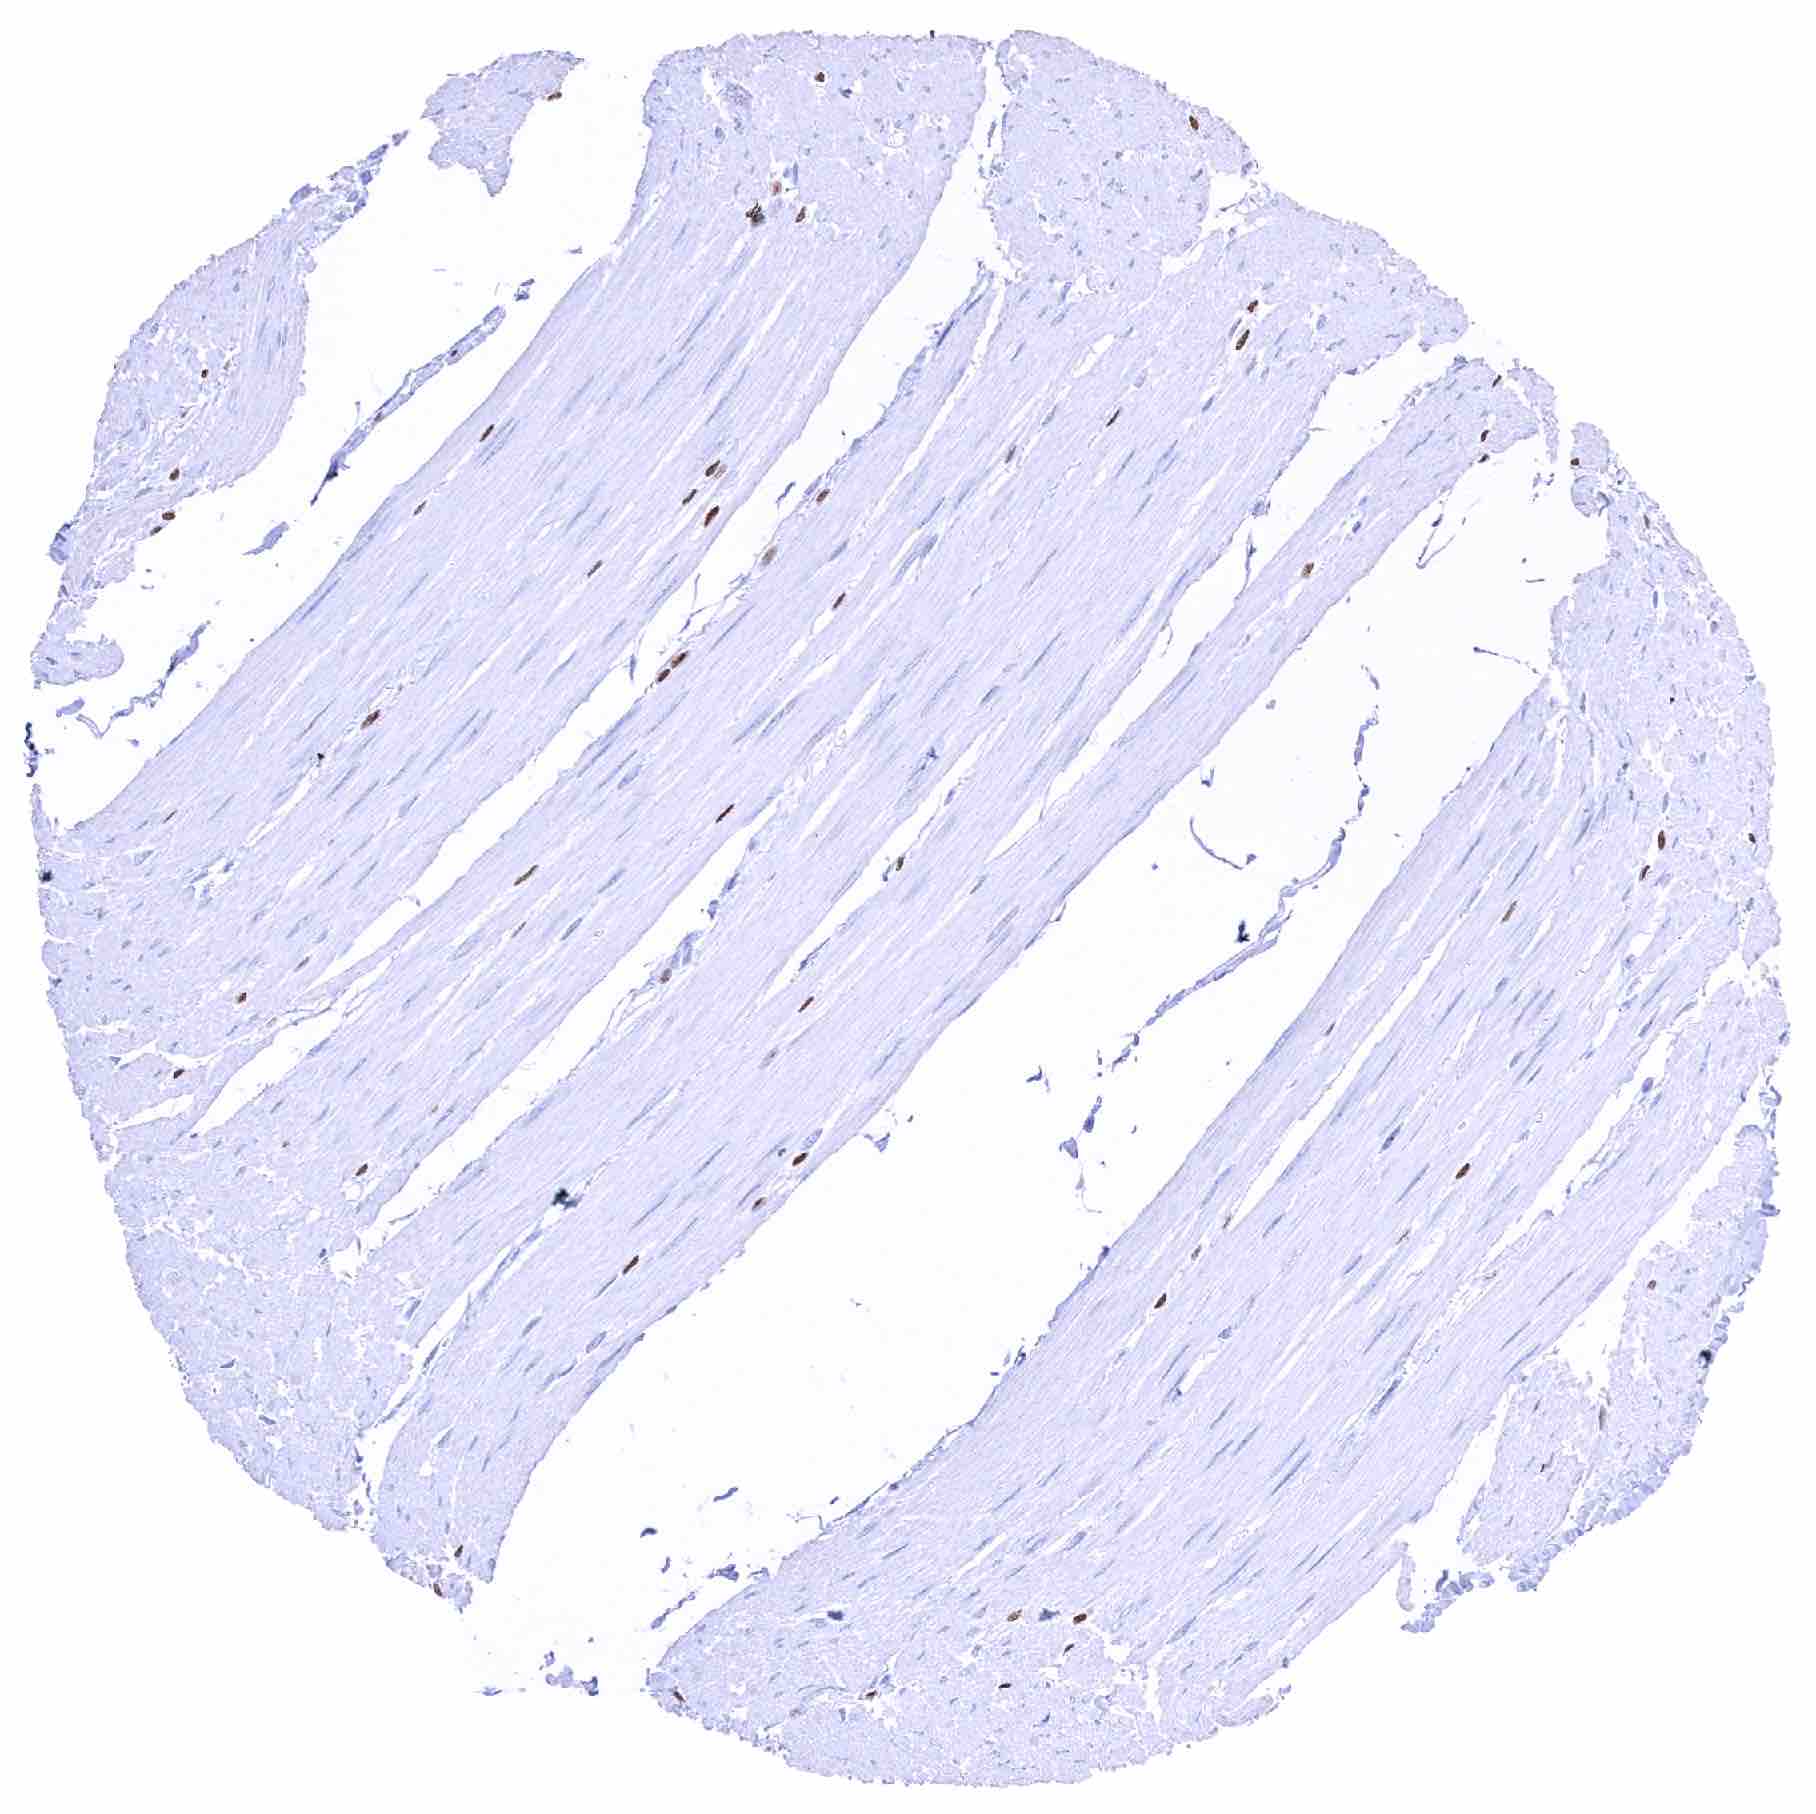

Skeletal muscle